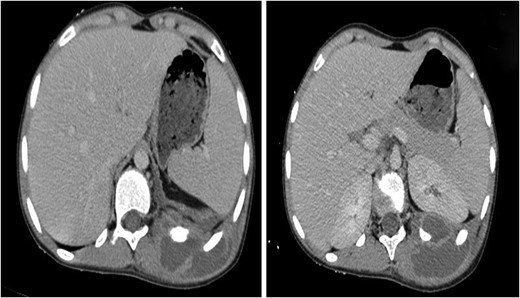

A 13-year-old female child was presented to the pediatric emergency unit with a painful swelling of the posterior left chest wall during the last 3 months. The patient was febrile without weight loss. She had a history of cutaneous mycosis for 2 years. The physical examination revealed a child in good general condition, febrile (axillary temperature was 38.2°C) and a painful swelling of the left posterior chest wall of ~6 × 4 cm2 (Fig. 1). The laboratory studies found a hemoglobin and hematocrit level of 10.5 g/dL and 34.4%, respectively, and a white blood cell count (WBC) of 15.210/μL with 80% neutrophils. Inflammatory indices such as erythrocyte sedimentation rate and C-reactive protein were greatly increased, with a level of 50 mm/h and 111 mg/L, respectively. The chest and the abdominal radiographs were found to be normal (Fig 2). The ultrasound showed an echogenic collection of the posterior chest wall of ~5 cm × 5 cm. A computed tomography (CT) scan of the chest with intravenous (IV) contrast showed a 6-3-5 cm pus collection of the posterior costovertebral region consistent with an osteomyelitis of the 10th, 11th, 12th ribs and soft tissue collection (Fig. 3). The abscess was incised and drained. A rib biopsy and a cytological examination of the pus were performed. Postoperatively the abscess was drained by a chest tube for two days before being removed. Postoperative antibiotic therapy with ceftriaxone, gentamicin and metronidazole was initiated. The pus culture was negative. Mantoux test and HIV test were negative. The histological examination of the rib biopsy disclosed a diagnosis of acute non-specific rib osteomyelitis. The patient was discharged after 2 weeks from hospital and the injection antibiotics were switched to oral administration (amoxicillin-acid clavulanic 80 mg/kg/day) for 6 supplementary weeks. The patient remains asymptomatic 6 months postoperatively.

Soft tissue and bone windows of a chest CT scan show a 6-3-5 cm pus collection of posterior chest wall. The mass appeared to traverse kidney capsule and the thoracic cage to be continuous with a pleural-based mass adjacent to it.